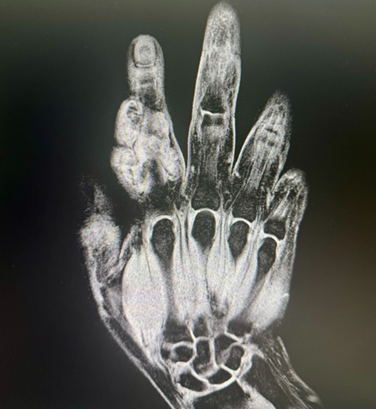

We present the case of a 41-year-old female patient with a history of systemic arterial hypertension treated with amlodipine and losartan once a day. She began approximately a year ago with a growing, initially as a painless mass on the index finger of the right hand. The slow-growing tumor continued to increase in size and was accompanied by pain at the fingertip, as well as paresthesia during hand activity, limitation of range of motion and sensation of blocking or clicking. She comes to our office and after the medical examination (Figure 3), we request an ultrasound and an MRI to assess the involvement of the neurovascular unit of the finger prior to the surgical approach.

Patient underwent surgery with an S-shaped dorsal access approach above de middle phalanx and extending proximally to the proximal interphalangeal joint. With careful dissection it was observed that the lesion involved ulnar digital nerve, while sparing the extensor tendon complex (Figure 4).

After releasing the edges of the lesion, while avoiding vascular and nerve structure the tumor mass was sectioned horizontally so it could be removed completely (Figure 5). Subsequently, the specimen was sent for histopathological examination, which confirmed the diagnosis of GCTTS.

It is worth noting that in this patient the tumor displaced the neurovascular structures and even surrounded them, so the plastic surgeon's expertise in hand surgery is the main point to highlight for the patient's adequate outcome.

Figure 3: GCTTS.